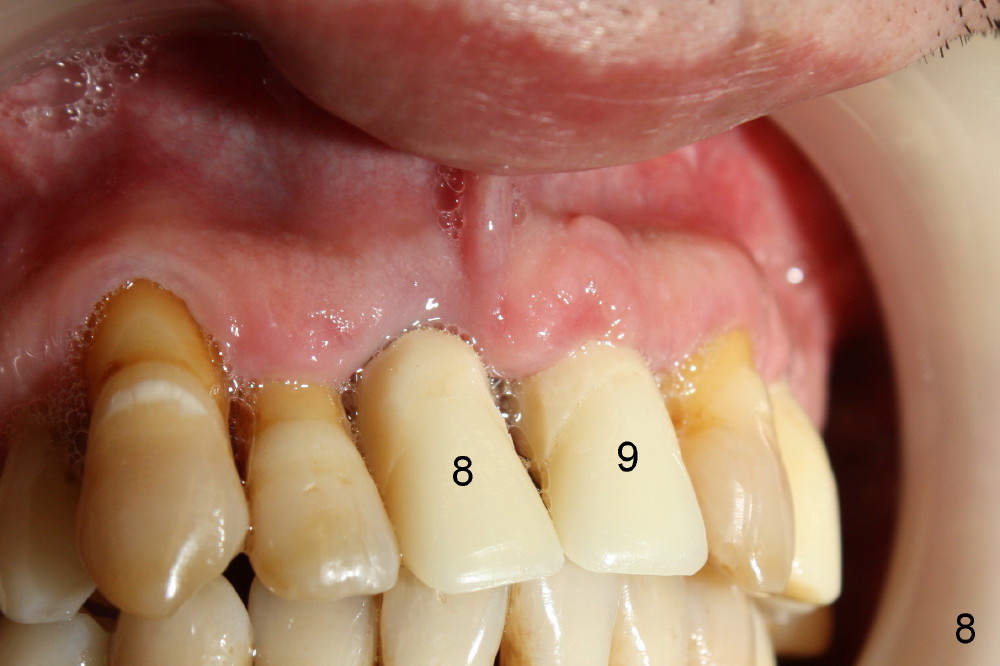

The insertion torque for the implants (4.5x20 mm and 4x20 mm) are 40 and 60 Ncm for #8 and 9, respectively (Fig.7). The stability is probably due to the fact that these two implants are engaged into the two cortical plates of the sockets (arrowheads). Allograft is placed in the mesiodens sockets. Immediate provisionals are fabricated. Fig.8,9 show the provisionals 18 days postop. One of the provisionals (#8) is dislodged 5 weeks postop. Before recementation of the provisional (Fig.10), healthy granulation tissue is found next to the implant (^).